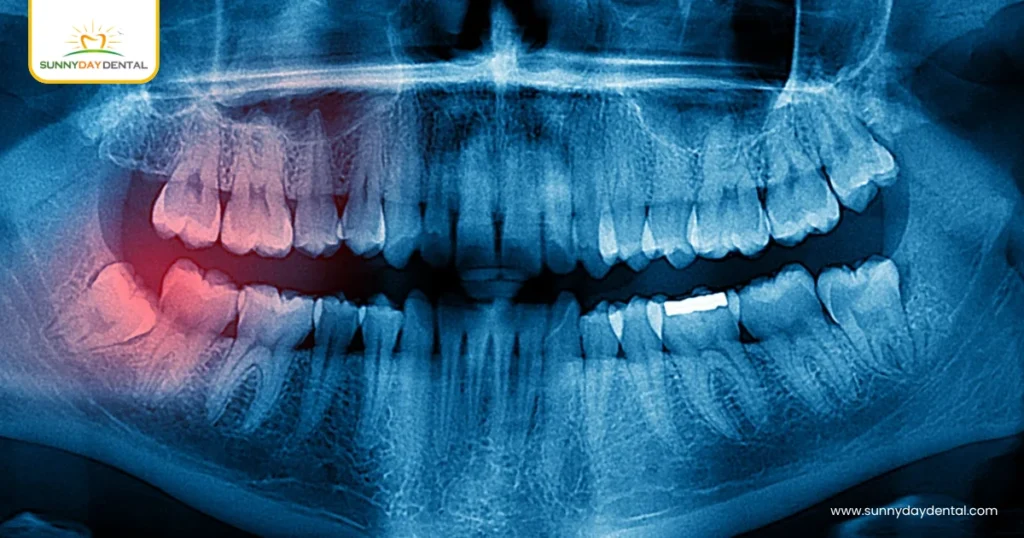

Prevention: The Role of Early Diagnosis

Regular dental X-rays can spot developing impactions before they cause pain or damage. At Sunny Day Dental, panoramic imaging is part of every young adult’s preventive plan — so potential impactions can be managed before they turn problematic.

- Imaging: Scans to check for cysts or bone lesions near impacted wisdom teeth.